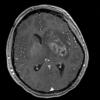

Mucormycosis - Zygomycosis